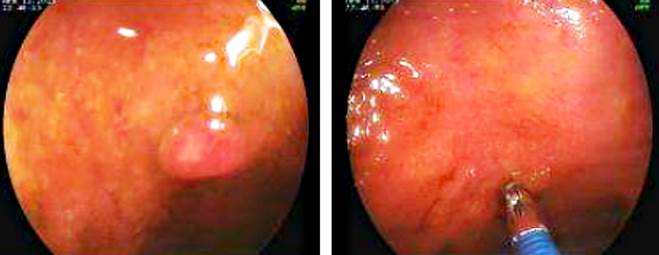

The ileocolonoscopy revealed nodular lesions measuring 3 to 5 mm in the distal ileum (Figures 3 and 4). Endoscopic resection of one of the lesions was performed (Figure 4), and the sample was sent for histopathological analysis. The remaining segments examined, including the cecum, ascending colon, transverse colon, descending colon, sigmoid colon, and rectum, showed no evidence of inflammatory or tumoral lesions. Haustral markings and colonic motility were preserved. Internal hemorrhoids were observed in the anal canal, without dilation or other abnormalities.

Gastrointestinal tumors that are difficult to distinguish from neurofibromas macroscopically and radiologically include lipomas, which account for 5% of all gastrointestinal tumors and 10% of benign gastrointestinal tumors. These lesions are typically located just beneath the mucosa and are usually asymptomatic. However, they can cause obstruction, intussusception, or bleeding. Lipomas may coexist with gastrointestinal neurofibromas, making them an important differential diagnosis to consider15,16. In the case reviewed in this article, atypical intestinal lesions were observed in the distal ileum of a 55-year-old female patient with NF1.